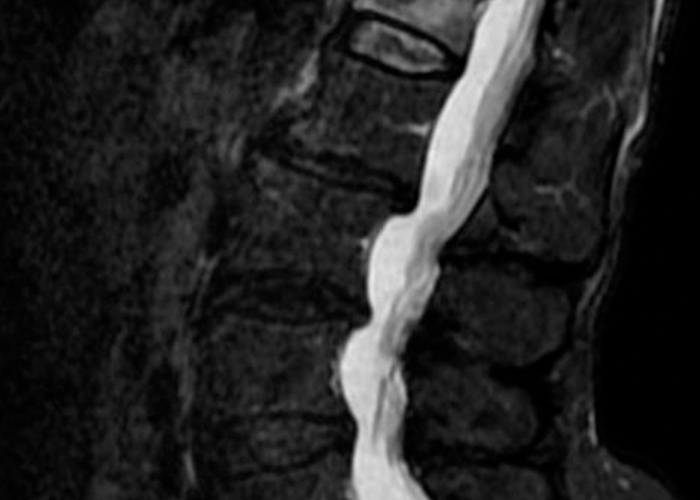

Una vez realizadas las pruebas de imagen, estas muestran una fractura acuñamiento de la 1º vértebra lumbar L1 sin que se vea afectado el muro posterior y con signos de edema agudo. Se decide realizar una cifoplastia.